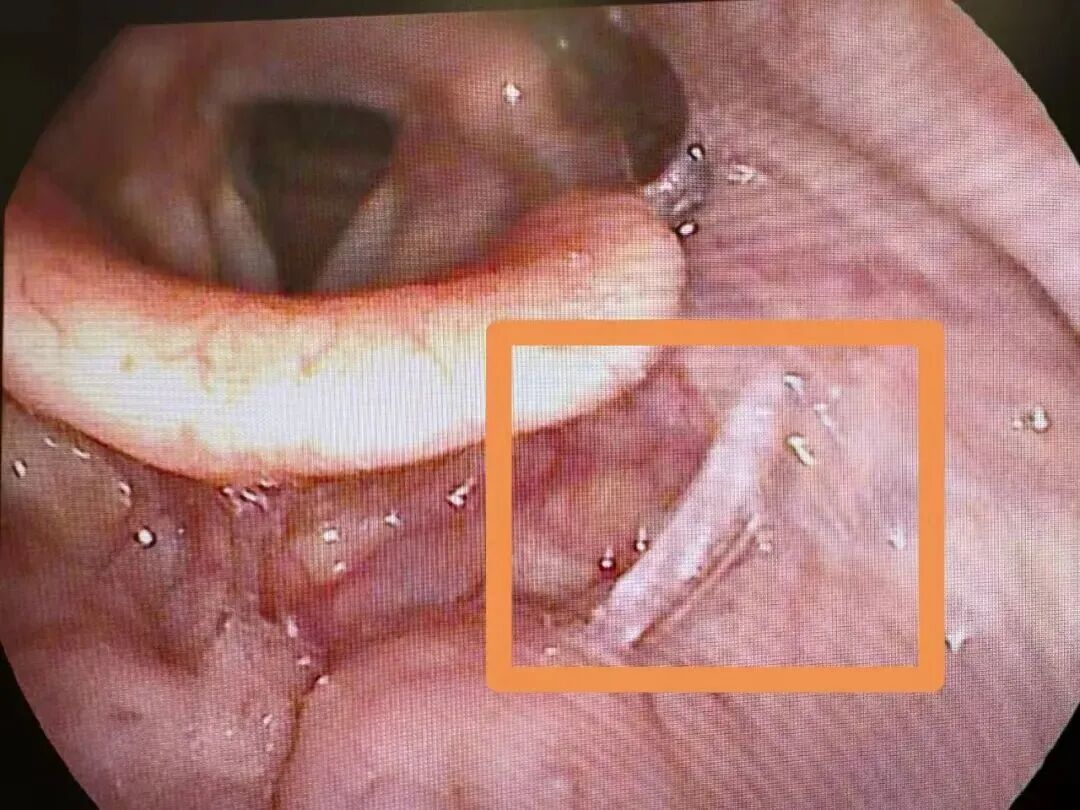

万幸的是,经过郭医生的专业处置,成功将带血的碎骨取出,小文终于能大口呼吸了,此时的他睫毛上还挂着未干的眼泪。“汤饭里的碎骨、鱼刺一定要仔细挑,孩子吃饭千万要小心!” 郭医生指着托盘里的碎骨,向小文妈妈郑重叮嘱道。

郭医生介绍,因误食碎骨、鱼刺等导致喉部异物,进而引发不适甚至损伤的情况,在临床上并不少见,尤其在食用“汤泡饭”时更容易发生。

近一个月,萧山区一医院急诊接诊的相关病人就有800余例。其中,大部分患者的异物位置较浅,可通过异物钳直接取出,但也不乏因异物卡得深、形态特殊,需借助软镜才能取出的案例,不仅治疗周期长,患者承受的痛苦也更多。